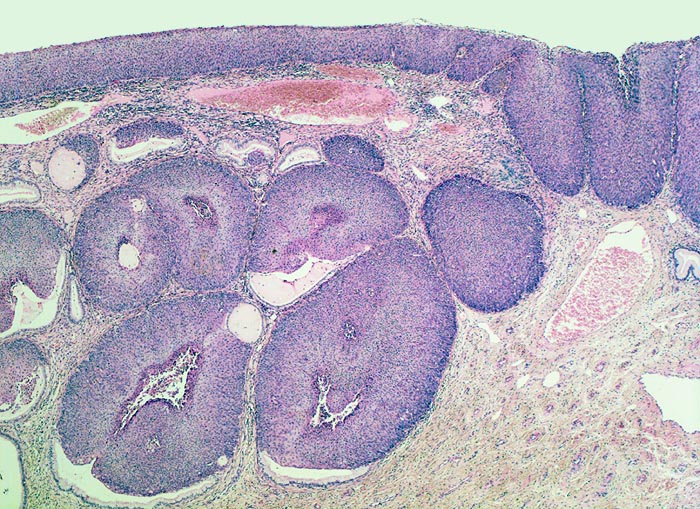

• Portio mit vorderer Muttermundslippe, Anteile der hinteren Muttermundslippe und Zervikalkanal.

• Carcinoma in situ der ektozervikalen Schleimhaut und des metaplastischen Plattenepithels im Bereich der Transitionalzone.

• Einwachsen des Carcinoma in situ in vorbestehende endozervikale Drüsenschläuche.

• Invasive solide Tumorzellstränge in desmoplastischem Stroma mit dichtem lymphoplasmazellulärem Entzündungsinfiltrat.

• Zellen des Plattenepithelkarzinoms mit vergrösserten, pleomorphen und hyperchromatischen Zellkernen, reichlich eosinophilem Zytoplasma und deutlichen Zellgrenzen.

• Zylinderepithel der endozervikalen Drüsen ohne Dysplasie. Das sollte der Kliniker dem Pathologen mitteilen: